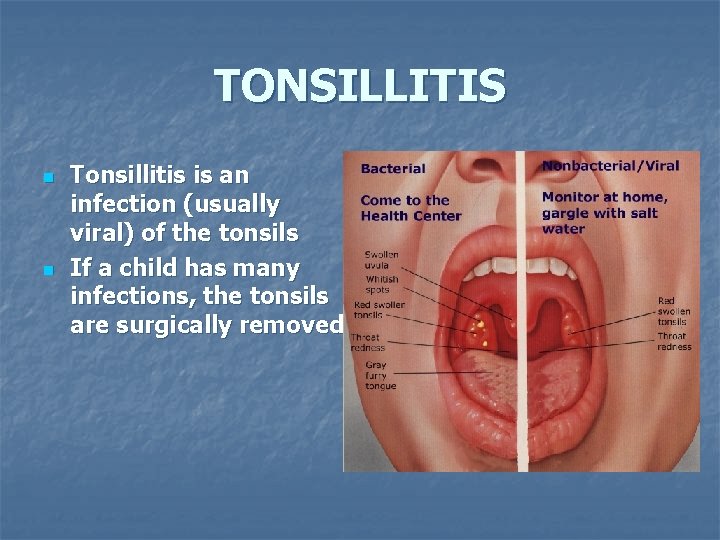

TONSILLITIS n n Tonsillitis is an infection (usually viral) of the tonsils If a child has many infections, the tonsils are surgically removed